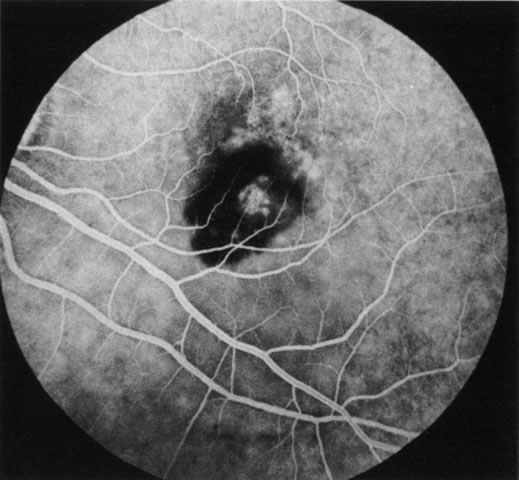

DIAGNOSIS Age-related macular degeneration (AMD) may be divided into two types. Nonexudative (“dry”) AMD has several morphologic forms, including “hard” discrete drusen, shallow retinal pigment epithelial detachments associated with thickened Bruch's membrane (“soft” drusen), and geographic atrophy (GA) of the retinal pigment epithelium (RPE).3 On FA the area of GA appears hyperfluorescent for window defect from the early frames of the angiogram, with late staining of the underlying sclera (Fig. 1). However, these pathologic changes can usually be assessed by clinical examination, and FA is generally not necessary to diagnose nonexudative AMD. An exception is cuticular drusen, which may appear clinically as a subtle disturbance of the RPE; FA reveals multitudes of small, discrete drusen described as “stars in the sky” (Fig. 2). The second type of AMD, which is associated with soft drusen, is known as exudative (“wet”) AMD. It is due to a choroidal neovascular membrane that has incompetent vessels resulting in detachments of the RPE and the neurosensory retina. Consequently, in patients with a large RPE and/or serous neurosensory detachment, FA is often necessary to rule out a choroidal neovascularization (CNV). In general, a small pigment epithelium detachment (PED) and a larger neurosensory detachment overlie CNV, while the opposite is generally the case in a nonexudative PED. Additionally, CNV often presents as a “notched” PED (Fig. 3).4 The presence of subretinal blood or pigment at the border of a PED strongly indicates that the detachment is exudative in origin (Fig. 4). Similarly, a rip in the RPE generally reflects subretinal fibrosis from a CNV (Fig. 5 and 6). The diagnosis is more difficult in patients who have a chronic, organized PED. Such a lesion may be due to either nonexudative AMD or to an organized, fibrotic CNV. Clinically and angiographically, it may be impossible to distinguish between these two conditions. In most cases, however, FA does assist in making the diagnosis.